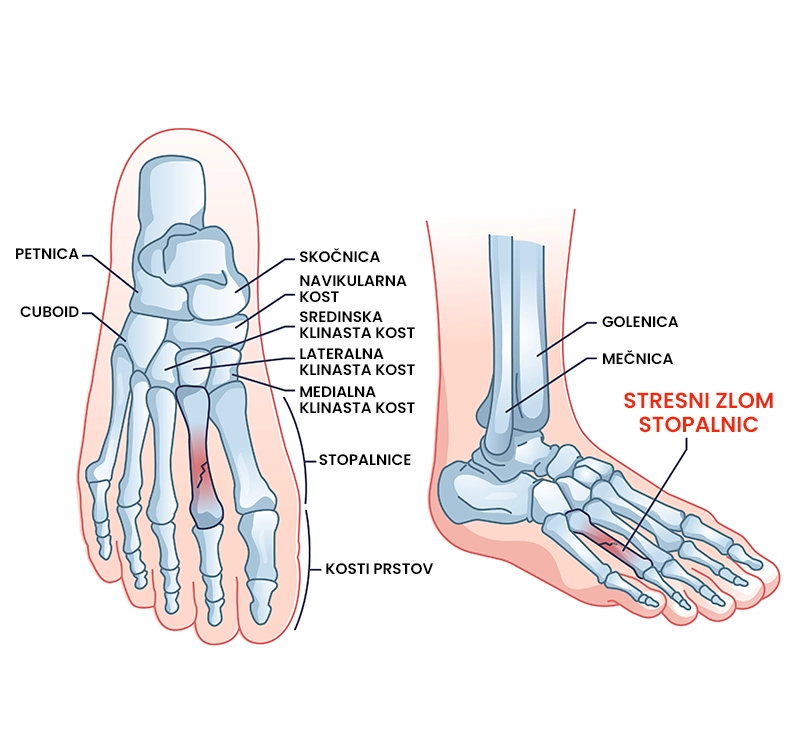

Zlom stopalnic (metatarzalnih kosti)

Kaj je zlom stopalnic?

Zlom stopalnic označuje nepopolni (stresni) ali popolni zlom ene ali več od petih stopalnih kosti. Zlom stopalnic je posledica akutne (npr. padec težkega predmeta na stopalo, skok z višine) ali kronične poškodbe (npr. ponavljajoč stres na stopalnice zaradi teka, korakanja,…). Poškodba se kaže kot bolečina ob obremenjevanju stopala in oteklina. Zlom stopalnic se pogosteje pojavlja pri otrocih, športnikih, ki jim je skupno veliko število pristankov na stopalnice (tek, gimnastika, balet, vojaki) in posameznikih s pridruženimi bolezni (osteoporoza – zmanjšanje kostne gostote kosti, revmatoidni artritis – avtoimuno kronično vnetje sklepnega hrustanca). 71 – 98 % posameznikov se po rehabilitaciji zloma stopalne kosti vrne nazaj na isto raven aktivnosti kot pred poškodbo.

Kako diagnosticiramo zlom stopalnic (diagnostični pregled)?

Zlom stopalnic diagnosticira zdravnik na podlagi anamneze, kliničnega pregleda in slikovne diagnostike. Fizioterapevt v okviru diagnostičnega pregleda potrdi verjetnost prisotnosti zloma stopalnic.

• Slikovna diagnostika v obliki rentgenskega slikanja (RTG) in magnetne resonance (MRI) se uporablja za opredelitev natančne diagnoze. RTG se uporablja za ugotavljanje prisotnosti zloma. MRI se opravi za izključitev pridruženih poškodb mehkih tkiv. Slikovna diagnostika lahko ne odkrije zloma zato se priporoča ponovno slikanje v primeru vztrajajočih simptomov po 2 do 6 tednih od prvega slikanja.